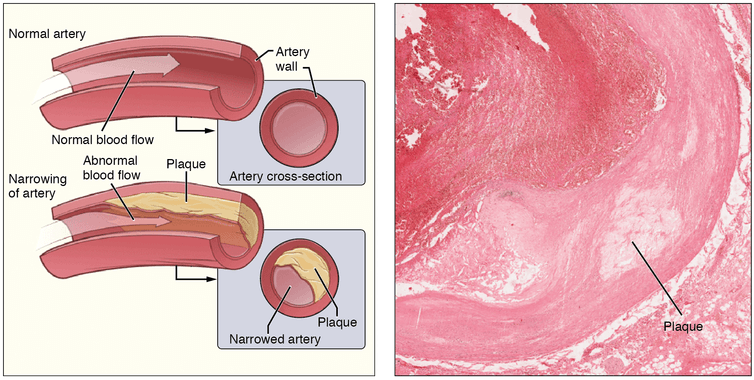

БОльшая часть пунктов этого списка серьезных заболеваний берет свое начало от атеросклероза артерий. Это состояние характеризуется накоплением в стенках артерий холестерина, продуктов распада клеток и ассоциированных с воспалением клеток, что затрудняет кровоток. Это ведет к блокированию кровотока кровяными сгустками (тромбозу).

Схематичное изображение и фотография артерии с атеросклеротической бляшкой.

Под действием таких повреждающих факторов, как табачный дым, плохое питание, сахарный диабет и других факторов риска эта барьерная функция может быть утрачена, что приводит к отложению и накоплению в сосудистой стенке различных компонентов атеросклеротических бляшек.

Атеросклероз коронарных артерий вызывает сужение просвета сосудов, что в конечном итоге может приводить к блокаде кровотока. В данном случае возраст далеко не всегда является критическим фактором, однако этот процесс усугубляется с возрастом и чем продолжительней воздействие факторов, тем с большей вероятностью развивается заболевание сердца.

Атеросклероз является первопричиной развития большинства болезней сердца, от которых страдают современные люди.